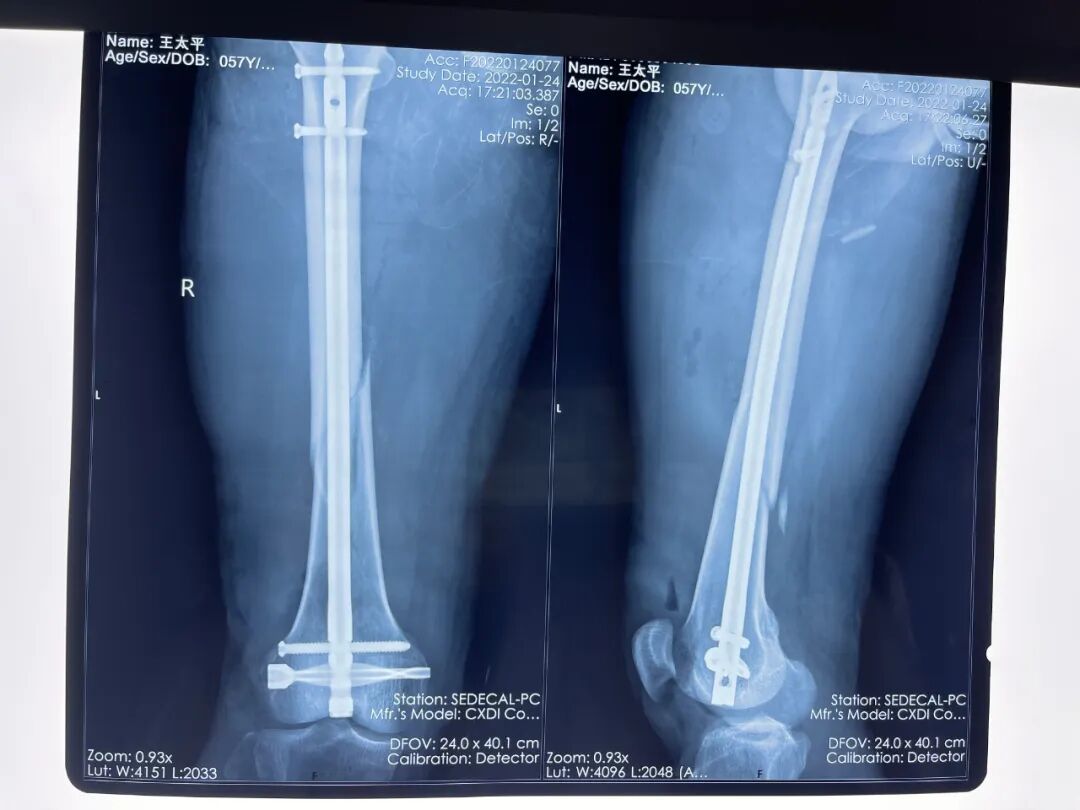

王明主任召集科室全體醫(yī)生進行了認(rèn)真的術(shù)前討論和充分準(zhǔn)備,最終決定應(yīng)用股骨遠(yuǎn)端逆行髓內(nèi)釘技術(shù)進行閉合復(fù)位內(nèi)固定手術(shù)。手術(shù)開始后,劉智副主任首先于膝關(guān)節(jié)前方開縱行小切口,于股骨髁中央向近端插入逆行髓內(nèi)釘,團隊三人共同努力下通過髓內(nèi)釘將遠(yuǎn)端整體與近端骨折塊進行復(fù)位,最后依次將遠(yuǎn)端和近端的多枚鎖定螺釘牢牢固定,股骨髁上并采用了螺旋刀片式橫鎖定釘更具穩(wěn)定性。由于采用微創(chuàng)內(nèi)固定的方式,手術(shù)用時僅2小時,幾處小切口的出血量也很少。經(jīng)過術(shù)后精心的護理和康復(fù)治療,王先生目前已順利康復(fù)出院。

術(shù)后

治療的目的是要對骨折進行精確復(fù)位和可靠固定。如果選用傳統(tǒng)的鋼板固定,這個患者的手術(shù)切口需要從膝部一直延伸到近髖關(guān)節(jié),三四十厘米長的手術(shù)切口不僅損傷大、出血多,而且鋼板固定的強度有限,術(shù)后不能進行積極的功能鍛煉,免不了長期臥床;如果選用普通的股骨順行髓內(nèi)釘,當(dāng)進釘?shù)竭_(dá)股骨髁部骨折端時,髓腔呈“喇叭口”樣擴張,單平面的兩枚鎖定螺釘并不能提供足夠的固定強度,髓內(nèi)釘很有可能在髓腔內(nèi)左右搖擺,造成固定失效甚至骨折不愈合。

剛接診這個患者的時候,采用逆行倒打髓內(nèi)釘手術(shù)方式我們也倍感壓力。但后來經(jīng)過科室的全體討論并查閱了大量資料后,大家一致認(rèn)為應(yīng)用股骨遠(yuǎn)端倒打髓內(nèi)釘系統(tǒng)進行微創(chuàng)內(nèi)固定是最佳的手術(shù)方案。該手術(shù)方式對骨折端進行閉合復(fù)位,避免了大切口,減少了出血量,減輕了患者的痛苦。同時髓腔內(nèi)的中心型固定結(jié)合螺旋刀片鎖定螺釘?shù)脑O(shè)計大大增強了固定的穩(wěn)定性,術(shù)后幾天,患者就可以在床上坐起活動,并開始下地扶拐主動的康復(fù)鍛煉了。即使同一部位的骨折,臨床表現(xiàn)也是千變?nèi)f化、紛繁復(fù)雜。對于每一個患者,可能有很多種治療方法,但是我們追求的目標(biāo)是給予患者最適合、最安全、最有效的方法。股骨遠(yuǎn)端倒打髓內(nèi)釘系統(tǒng)的引進,為復(fù)雜股骨干骨折、股骨遠(yuǎn)端骨折甚至部分股骨髁上、髁間骨折的治療提供了新的思路,可以實現(xiàn)微創(chuàng)化、精準(zhǔn)化的生物學(xué)固定,與傳統(tǒng)手術(shù)方法相比具有明顯優(yōu)勢,也符合現(xiàn)代外科學(xué)個體化、微創(chuàng)化治療的發(fā)展趨勢。